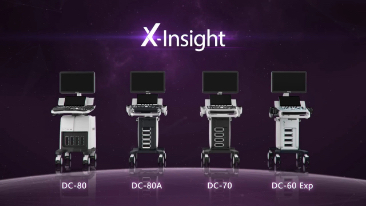

Ultrasound System

DC-70

X-Insight

Overview

X-Insight is an insightful solution to envision more.

MindrayŌĆÖs brand-new solution is an excellent transforming of continuous customer insights into clinical needs, combined with evolving cutting-edge ultrasound technologies.

As an intimate partner, DC-70 with X-Insight focuses on what matters to you, helping you manage your daily clinical practice with ease and certainty.

Based on deep insights into customer needs, the DC-70 with X-Insight is designed to deliver high efficiency with precision imaging, which is empowered by eXpress Clarity and eXceptional Intelligence, and benefits from eXceeding Experience.